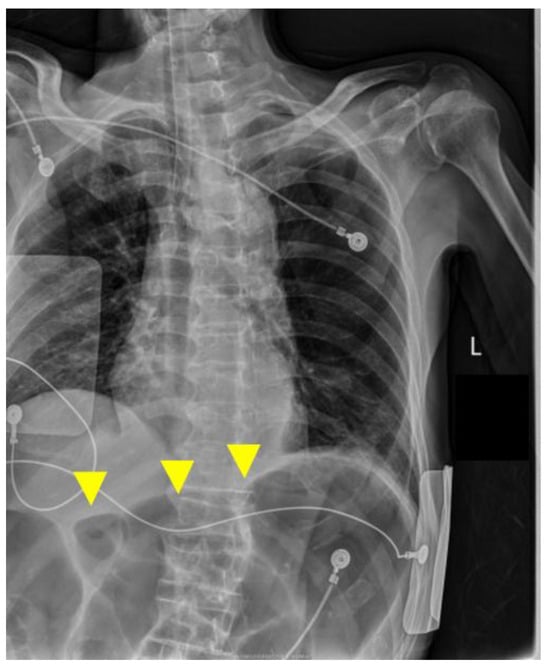

A portable anteroposterior chest radiograph obtained immediately after intubation confirmed appropriate endotracheal tube position and showed no new diffuse bilateral infiltrates suggestive of acute respiratory distress syndrome (ARDS) or marked progression of pneumonia. In contrast, the upper abdomen demonstrated markedly dilated gas-filled bowel loops consistent with colonic distension, likely involving the transverse colon (Figure 4). Following a discussion with the family, a do-not-resuscitate order was confirmed, CPR was discontinued at 05:44, and death was pronounced at 06:15. The death certificate listed acute heart failure as the immediate cause of death.

Figure 4.

Portable chest radiograph at the time of intubation on postoperative day 4. Yellow arrows indicate markedly dilated gas-filled bowel loops in the upper abdomen, consistent with colonic gas distension.

The anteroposterior bedside chest X-ray confirmed the appropriate position of the endotracheal tube and showed no new diffuse bilateral infiltrates suggestive of acute respiratory distress syndrome (ARDS) or marked progression of pneumonia. The upper abdomen shows markedly dilated gas-filled bowel loops, most prominent in the transverse colon region; although interpretation is limited on a portable chest radiograph, this finding is considered supportive of possible abdominal pathology in a clinical picture compatible with sepsis.